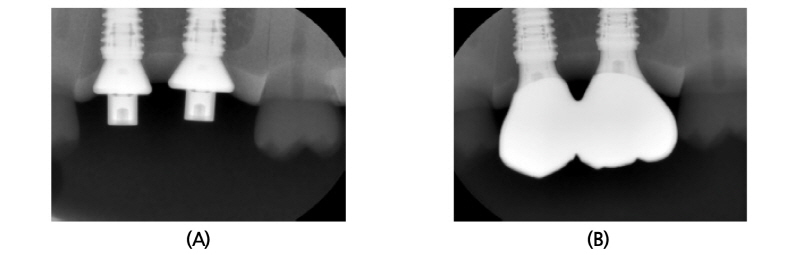

코딩되어 있다는 의미는 임플란트 식립 깊이, hex 방향, 임플란트 platform 직경 등과 같은 임플란트 식립체에 관한 정보가 내장되어 있다는 것이다. 전통적인 치유 지대주와 달리 코딩된 치유 지대주는 별도로 분리되는 나사(abutment screw)를 매개로 임플란트 식립체와 연결된다는 특징이 있다(Fig. 1).

최종 모형과 인상용 코핑, 그리고 임플란트 아날로그 등의 제작 또는 사용 없이 인상을 채득할 수 있는 방법이다(Fig. 2, 3).